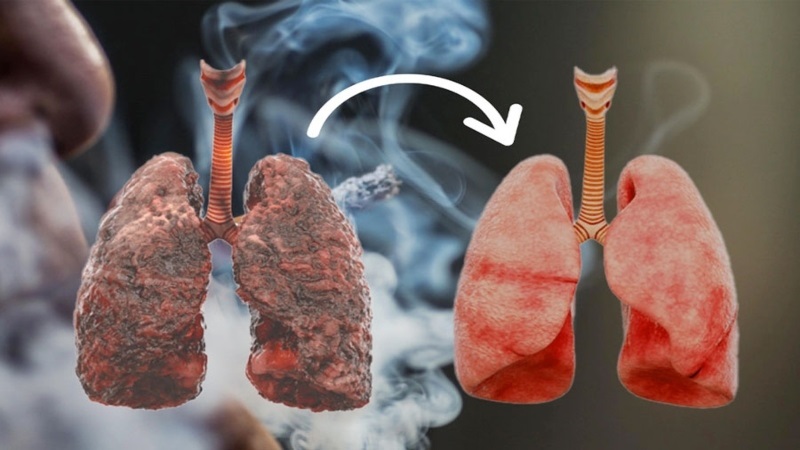

ফুসফুসের স্বাস্থ্য নিয়ে আলোচনা হলে প্রথমেই আসে ধূমপানের কথা। কারণ ধূমপান সরাসরি ফুসফুসে ক্ষতি করে। কিন্তু বিশেষজ্ঞরা বলছেন, ধূমপানই একমাত্র ক্ষতিকর নয়, আমাদের আরো কিছু প্রতিদিনের অভ্যাসও ফুসফুসের জন্য বিপজ্জনক হয়ে উঠছে। চলুন, জেনে নিই।

ধূমপান ছাড়া আরো যেসব কারণে ক্ষতিগ্রস্ত হতে পারে ফুসফুস

- ১। ধূমপান থেকে দূরে থাকুন।